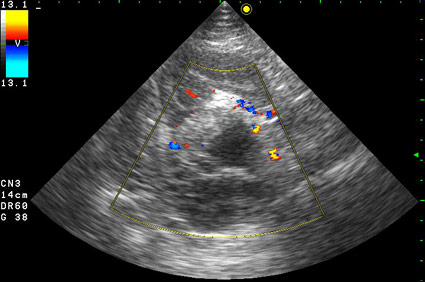

Образование в режиме ЦДК.